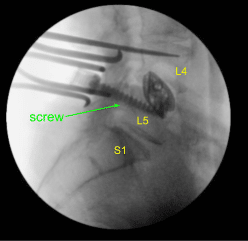

Dada la preocupación por el implante en decúbito prono y nuestra sensación de que las placas terminales pueden haberse fracturado más, expusimos los procesos transversales para L4 y L5 y utilizamos el taladro para crear orificios piloto en el pedículo en el lado izquierdo en L4 y L5. Bajo fluoroscopia, guiamos las sondas a través de los pedículos y golpeamos cada pedículo, luego colocamos tornillos pediculares en L4 y L5.

Estos tornillos fueron estimulados y revisados bajo fluoroscopia, y luego se colocó un montado y se apretaron los tornillos de la tapa. En el lado derecho e izquierdo, decorticamos las facetas y los procesos transversales y colocamos nuestra masa de fusión para la artrodesis.